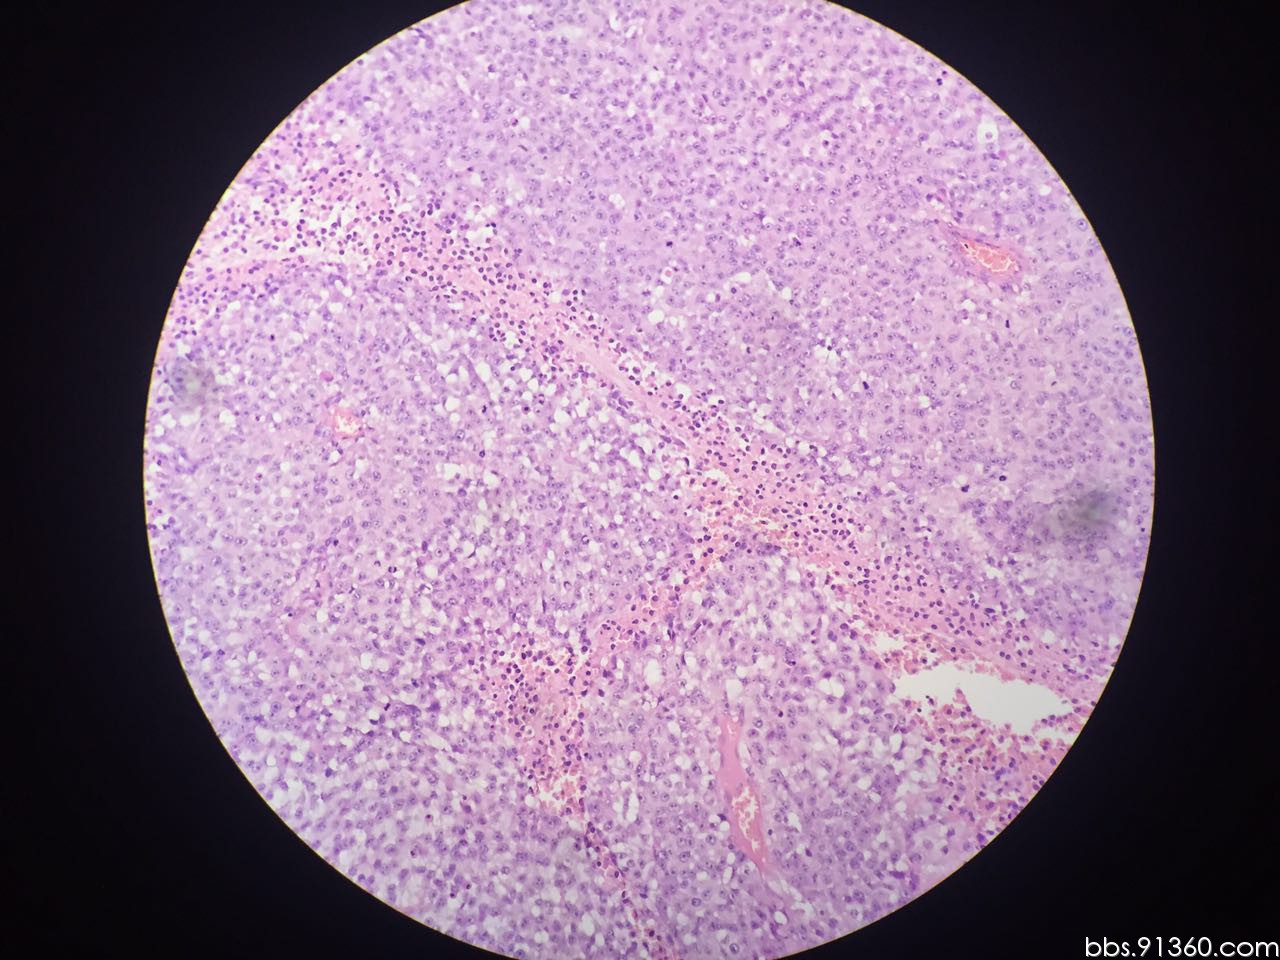

左大腿根部 精原细胞瘤 9.8【91360软组织与骨沙龙病例94】